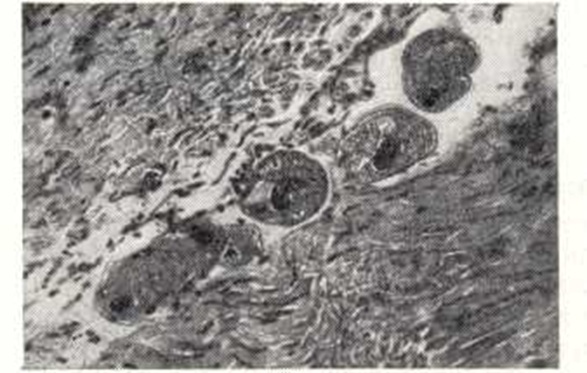

При присоединении бактериальной инфекции процесс может закончиться гангреной кишки. При надавливании на края язв и эрозий выделяется гнойное отделяемое. При Б. иногда поражается червеобразный отросток с клинической картиной острого аппендицита и нахождением балантидии в воспаленной его стенке. В начале заболевания на слизистой оболочке кишки появляются участки гиперехмии и отека, на к-рых возникают эрозии и язвы. Эпителий кишечных (либеркюновых) желез начинает усиленно пролиферировать и некротизироваться. В окружающих тканях появляется лимфоцитарный инфильтрат, к-рый, как и ткани, некротизируется, формируются эрозии, к-рые могут зажить или прогрессировать и вести к образованию язв. При проникновении инфузорий в подслизистую основу в тканях возникает воспалительный отек, кровоизлияния и инфильтрат из лимфоцитов, гистиоцитов и сегментоядерных лейкоцитов, местами формируются мелкие сливающиеся абсцессы. Язвы при Б. развиваются не одновременно: наряду с острыми язвами имеются рубцующиеся и рубцы на месте заживших язв. Паразиты обнаруживаются в краях язв, криптах желез и толще подслизистой оболочки. В мышечном слое кишечника (рис. 3) они обнаруживаются реже. Описаны также поражения тонкой кишки, миокарда, печени, почек. При обычных гистологических окрасках в пораженных тканях балантидии обнаруживаются даже спустя 24—28 час. после смерти. При дифференциальной диагностике балантидии и паразитических амеб следует помнить, что балантидии крупнее, ядро у них бобовидное, богатое хроматином, цитоплазма базофильная, содержит вакуоли. Для гистологического исследования и установления этиологического диагноза берут край язвы кишки, в тканях к-рой обнаруживают балантидии. Делают также мазки из отделяемого язв и толщи стенки кишки. Патогенез. Проникнув в организм человека через рот, балантидии локализуются в толстой кишке — преимущественно слепой кишке, реже в нижнем отделе тонкой кишки. Размножаясь в просвете кишки, они могут не вызывать отчетливо выраженных симптомов болезни, что ряд авторов расценивает как носительство. Однако при тщательном обследовании таких лиц в большинстве случаев выявляется субклиническое течение Б. При внедрении балантидии в слизистую оболочку толстой кишки образуются характерные язвы и развиваются клинические симптомы болезни. Проникновению балантидии в глубь тканей способствует фермент гиалуронидаза, к-рый они образуют в процессе своей жизнедеятельности. Экспериментально установлено, что миграционный аскаридоз также благоприятствует внедрению балантидии в глубь слизистой оболочки кишки (В. В. Богданович, 1962). Клиническая картина. Различают субклиническую, острую, хрон. рецидивирующую и непрерывно текущую формы Б.; в очагах возможно носительство В. coli. При субклиническом Б. кишечных расстройств не бывает, больные считают себя здоровыми. Однако при ректороманоскопии у них нередко обнаруживаются катарально-геморрагические и характерные язвенные поражения в дистальном отделе толстой кишки. Выявляются нарушения функций печени, явления гипо- и авитаминоза С и эозинофилия в крови. Острый Б. протекает в большинстве случаев тяжело с наличием интоксикации, лихорадки, головных болей, тошноты, рвоты. Стул жидкий, обильный, от 8—10 до 20 раз и более в сутки, испражнения нередко имеют гнилостный запах, примесь слизи и крови. Больных беспокоят боли в животе, они быстро теряют в весе, Наблюдается общий упадок сил. При формах средней тяжести явления интоксикации менее выражены, стул 5—10 раз в сутки. Продолжительность острого Б. не превышает 2 мес; без лечения он переходит в хрон. форму. Для хрон. рецидивирующего Б. характерно чередование обострений от 7 —10 до 20—30 дней с ремиссиями в 3—б мес. От острого Б. он отличается более легким течением, отсутствием лихорадки, преобладанием кишечных расстройств над симптомами интоксикации. Без лечения болезнь может продолжаться 5— 10 и больше лет. Хрон. непрерывный Б. характеризуется постепенным развитием симптомов и вялым, монотонным течением, к-рое нередко приводит к истощению, а при отсутствии лечения — к кахексии. Наиболее грозные осложнения — перфорации балантидиазных язв и кишечные кровотечения — возникают редко, но часто имеют летальный исход. Диагноз ставится на основании клинической картины, данных ректороманоскопии, эпидемиологического анамнеза и обнаружения возбудителя в кале. Дифференциальный диагноз проводится с дизентерией (см.), амебиазом (см.), неспецифическим язвенным колитом (см. Язвенный неспецифический колит), реже с полипозом и раком кишечника. Прогноз в легких случаях благоприятный, в тяжелых — сомнительный. Лечение. Весьма эффективен мономицин по 150 000 — 250 000 ЕД, назначаемый внутрь четыре раза в сутки в течение двух пятидневных циклов с интервалом в 5 дней. При тяжелом течении Б. назначают внутрь мономицин с террамицином: первый по вышеуказанной схеме, второй — по 0,2 г четыре раза в сутки 7 дней; проводится не менее трех циклов с интервалом 5—7 дней. Лечение легких и среднетяжелых форм Б. можно проводить одним террамицином или биомицином. В качестве дополнительных средств можно применять аминарсон, ятрен, энтеросептол. С хорошим результатом у единичных больных применялись ампициллин, метранидазол. Назначение аскорбиновой к-ты внутрь и внутривенно повышает эффективность лечения; при хрон. формах Б. целесообразны переливания крови дробными дозами. Профилактика. Охрана окружающей среды от загрязнения необезвреженными фекалиями свиней; соблюдение сан.-гиг. правил при уходе за свиньями, своевременное выявление и лечение больных Б.